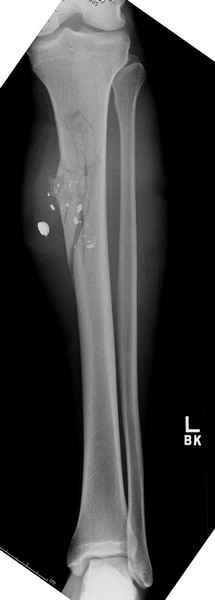

1 неполный перелом большеберцовой кости перкутанная пластина